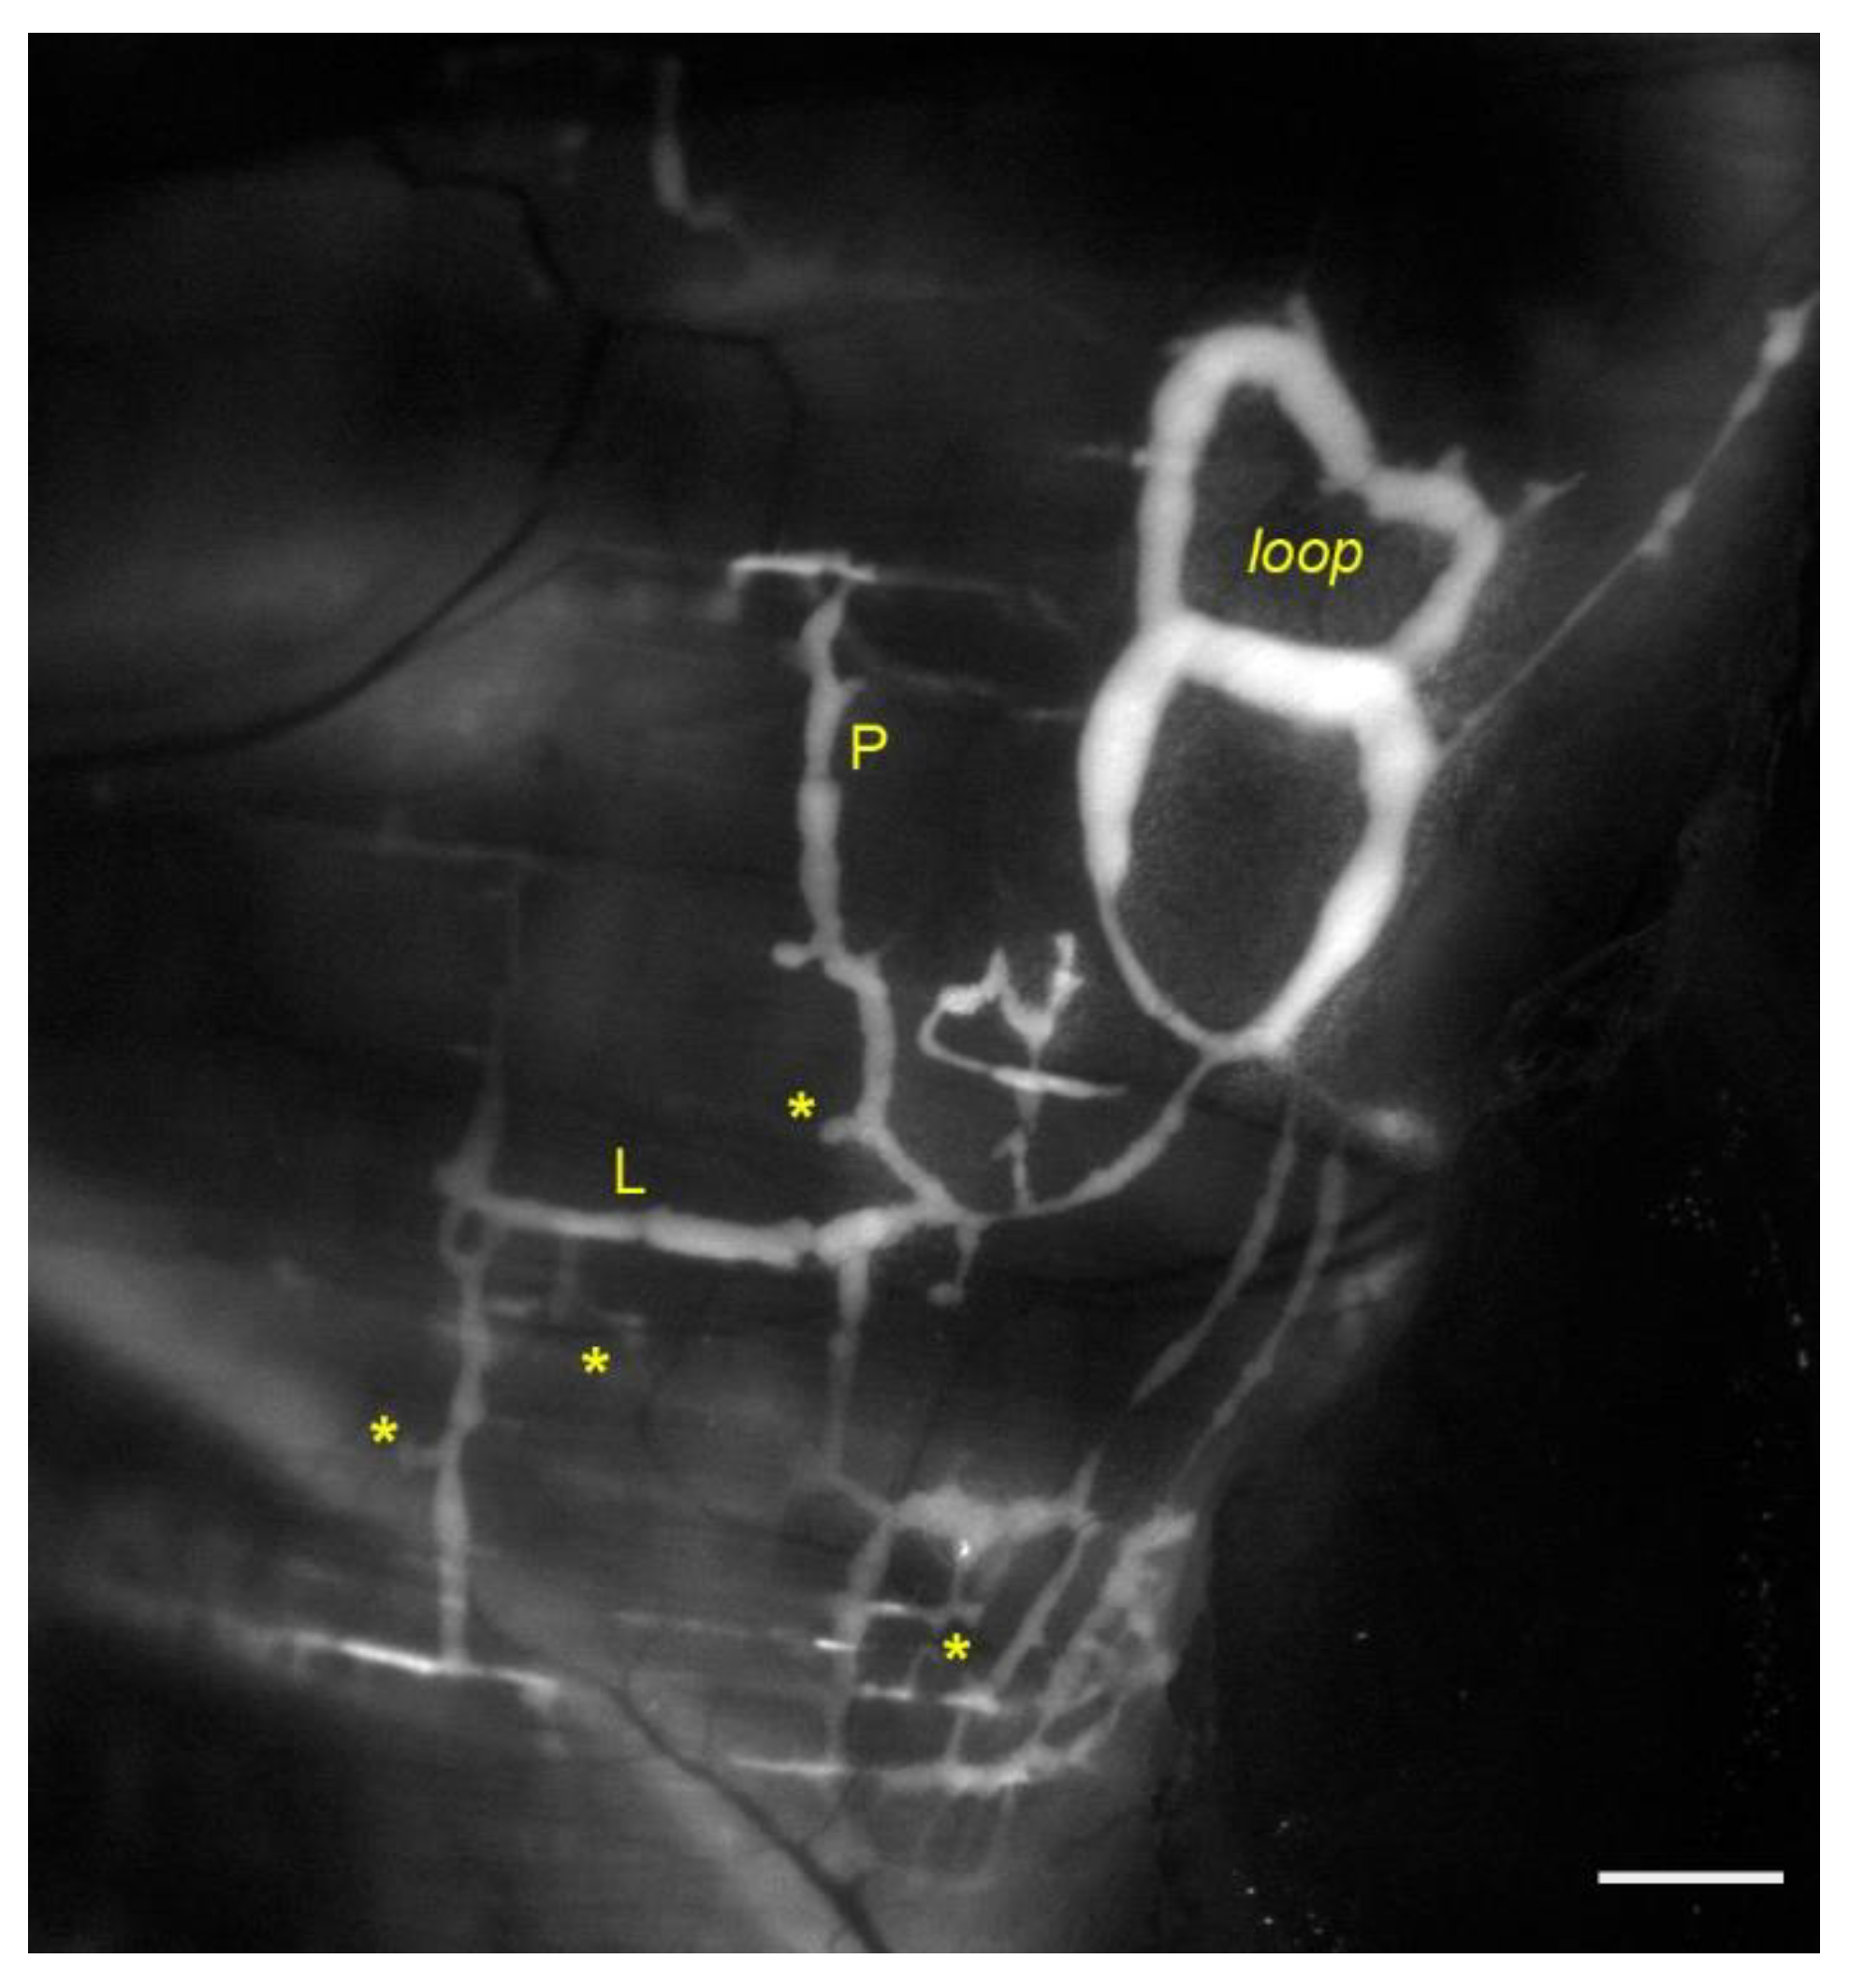

Figure 1.

Representative image of lymphatic vessels organization on the pleural side of rat diaphragm, after the in vivo staining with a FITC-conjugated fluorescent tracer. Lymph enters lymphatic lacunae (asterisks) and then is propelled through vessels longitudinally (L) and/or perpendicularly (P) arranged with respect to the skeletal muscle fibers orientation. Lymphatic collectors located at the muscle periphery, next to the costal margin, are typically organized in complex loop structures (loop) and display intrinsic contractility. Scalebar 1 mm.

In vivo PL recordings performed on rat pleural vessels while inducing active diaphragmatic skeletal muscle contractions [34] revealed that in superficial, perpendicularly oriented (Figure 1, P) lymphatic vessels each contraction of the diaphragm reduces the diameter by ~39%. This in turn causes a decrease by ~12 cmH2O in PL in submesothelial vessels, maybe enhancing the pressure gradient (ΔPTM) driving force thus favoring lymph formation. Conversely it induces PL increase by ~11 cmH2O in deeper perpendicularly oriented collectors, favoring lymph propulsion. In longitudinally oriented vessels (Figure 1, L) diaphragmatic muscle contractions reduce the vessels’ length by ~30% whereas the lymphatic diameter enlarges by ~23%. In these longitudinally oriented lymphatics, PL decreases in both superficial submesothelial and deeper vessels by ~22.5 cmH2O and ~10.5 cmH2O respectively, thereby supporting further lymph propulsion. The different regional effect may also be explained considering that deeper lymphatics are entirely surrounded by stiffer skeletal or tendinous fibers, thus displaying a compliance ~2 order of magnitudes lower than superficial vessels. Hence mechanical stresses are better transmitted to those lymphatics, with only minor wall deformation [32].